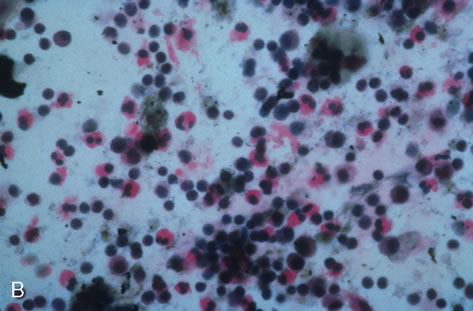

Clinical diagnosis of HSV infection can be made when the characteristic vesicular lesions are present. The diagnosis can be confirmed by isolation of the virus in tissue culture when necessary. Scraping the base of the lesions and Wright's, Giemsa, or Papanicolaou's stains will demonstrate the characteristic giant cells or intranuclear inclusions of herpesvirus infection.

Any cell type may be infected, appearing larger than normal (cytomegalic) and demonstrating eosinophilic intranuclear “owl's eye” and smaller intracytoplasmic viral inclusion bodies, which are better seen with Giemsa or Papanicolaou's stains (Fig. 8). Histologic examination of tissue specimens, including bronchoalveolar lavage fluid and urine, may be useful for diagnosis.